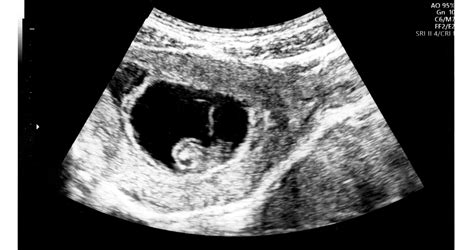

Pozitív terhességi teszt esetén mindenképpen forduljunk nőgyógyászhoz, mert csak ultrahangvizsgálattal lehet 100%-os bizonyossággal megállapítani a terhesség fennállását. Az első kismama-vizsgálatnak legkésőbb a 8. hétig meg kell történnie. Ha elmarad a menstruáció, de negatív a teszt, akkor is indokolt a kivizsgálás.